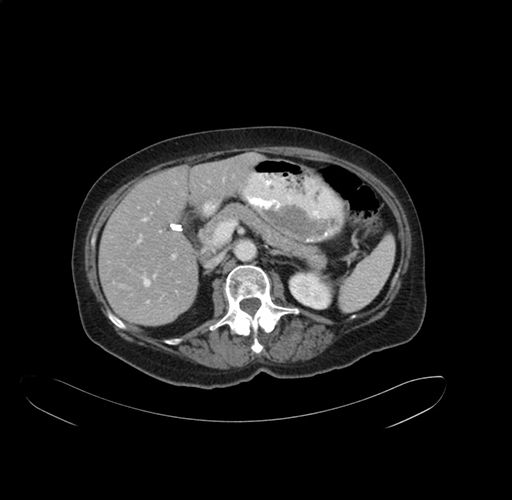

Pre-Chemo: Coronal Venous

Coronal Venous